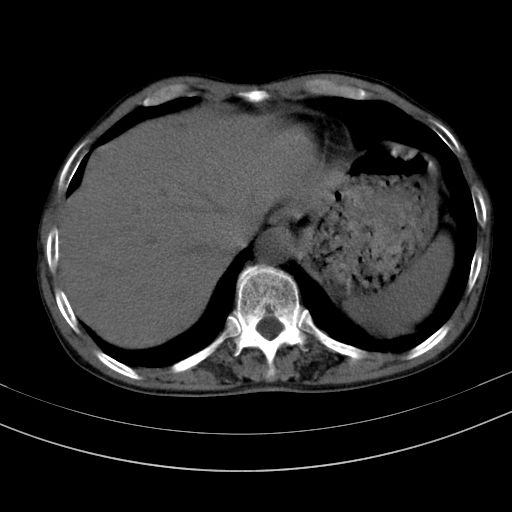

以下是引用37度在2010-1-9 14:37:00的发言:[br]1.双肾囊肿,左肾积水结石,.胆总管轻度扩张;[br]2.病灶在腹膜外,考虑纤维瘤。

以下是引用dyqct在2010-1-9 17:56:00的发言:[br]考虑:1.双肾囊肿,左肾积水结石、旋转不良。[br] 2.右侧腹直肌血肿或纤维瘤。[br]肠道准备不好。做个增强。